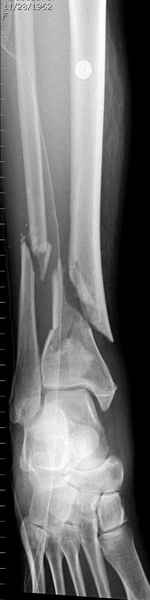

На снимках варианты фиксации малоберцовой:

№ 2-5 при огнестрельном переломе